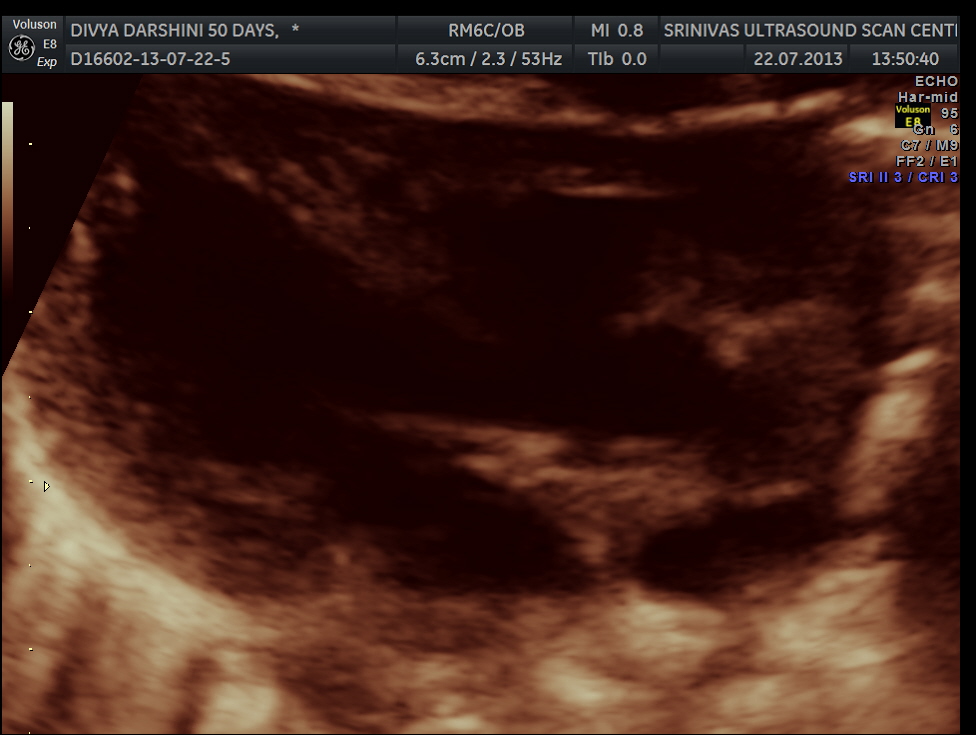

https://kriznanultrasoundimages.com/2013/05/12/tetralogy-of-fallot-tof/ at this time there was a revision of the cardiac findings : LEFT ATRIAL ISOMERISM WITH TETRALOGY OF FALLOT The irregular rhythm was not made out now. Apart from this the foetus has symmetrical IUGR and oligohydramnios Now the child was brought when she was 51 days old . She was born prematurely at 33 weeks of gestation . She had been seen at three higher institutions . The paediatric cardiologist has given a working diagnosis of CONO TRUNCAL VSD. But the catch was that the child had renal dysfunction with s .creatinine around 2 mgms and the ultrasound could not visualise the left kidney. The right kidney was reported to be hyperechoic . The following 2 pictures were of the fetal kidneys , as seen during the scan earlier.

The following two pictures show the hyperechoic kidneys of the child with mild pelvi calyceal dilatation . The kidneys were picked up only with the 11 mhz transducer.